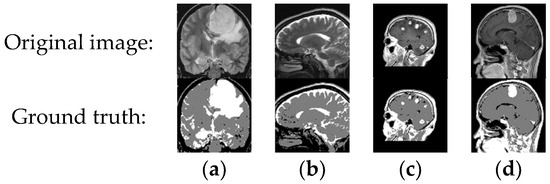

4.2.4. Medical Images

- Brain Tumor MRI Dataset. Available online: https://www.kaggle.com/datasets/masoudnickparvar/brain-tumor-mri-dataset (accessed on 16 March 2024).